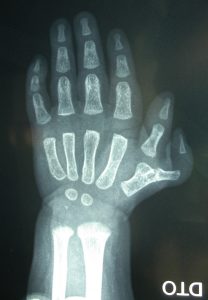

Fig. 1: Polidactilia do polegar

Polidactilia radial ou do polegar (existência de 2 polegares)

Polidactilia do polegar:

A polidactilia do polegar é a mais frequente na raça branca.

É quase sempre unilateral (ocorre apenas num dos lados) – na nossa casuística temos apenas uma criança com a deformidade bilateral (nas 2 mãos).